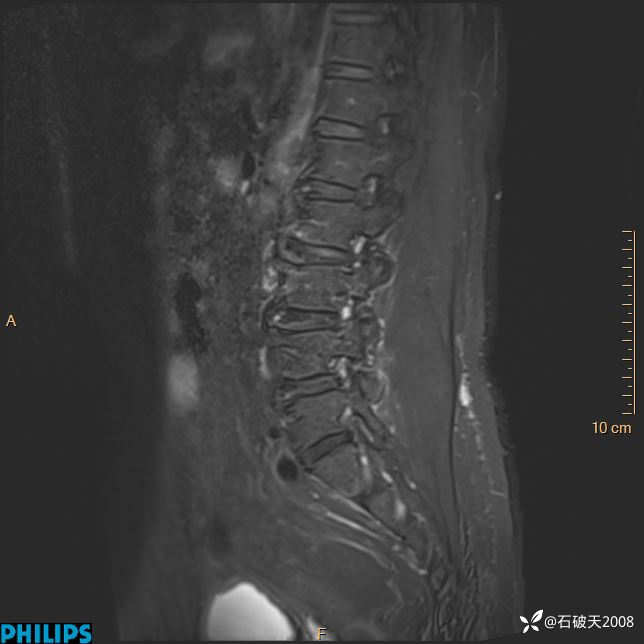

2023年3月份MRI影像

T1矢状位